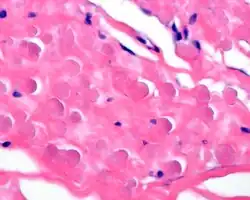

Pathology findings

In general, the tumor is an ill-defined, nonencapsulated, rubbery, and firm, white lesion with interspersed fat. The tumors can be quite large (up to 20 cm), although most are around 5 cm.[4]

By microscopie view, there is an admixture of heavy dense bands of collagenous tissue dissected by fat and abnormal elastic fibers. The elastic fibers are often quite large and are easily identified. The elastic fibers are coarse, thick, and darkly eosinophilic, often fragmented into globules, creating a "string of pearls" or "pipe cleaner" appearance. Because of degeneration, the elastic fibers will appear as globules with a serrated or "prickled" edge.[4]

Histochemistry

The elastic fibers will be highlighted by a Weigert or von Gieson elastic stains.[9]